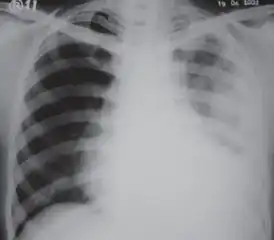

A fibrothorax can typically be diagnosed by taking an appropriate medical history in combination with the use of appropriate imaging techniques such as a plain chest X-ray or CT scan.[3] These imaging techniques can detect fibrothorax and pleural thickening that surround the lungs.[7] The presence of a thickened peel with or without calcification are common features of fibrothorax when imaged.[3] CT scans can more readily differentiate whether pleural thickening is due to extra fat deposition or true pleural thickening than X-rays.[3]

If a fibrothorax is severe, the thickening may restrict the lung on the affected side causing a loss of lung volume.[7] Additionally, the mediastinum may be physically shifted toward the affected side.[3] A reduction in the size of one side of the chest (hemithorax) on an X-ray or CT scan of the chest suggests chronic scarring.[6] Signs of the underlying disease causing the fibrothorax are also occasionally seen on the X-ray.[6] A CT scan may show features similar to those seen on a plain X-ray.[7] Lung function testing typically demonstrates findings consistent with restrictive lung disease.[6]

Chest radiograph displaying inhomogeneous opacification of the left half of the chest that is fibrothorax